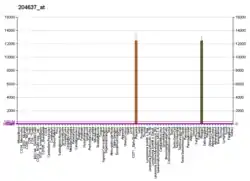

| Aliases | CGA, CG-ALPHA, FSHA, GPHA1, GPHa, HCG, LHA, TSHA, Chorionic gonadotropin alpha, glycoprotein hormones, alpha polypeptide, Alpha subunit of glycoprotein hormones, GPA1 | ||||||||||||||||||||||||||||||||||||||||||||||||||

| External IDs | OMIM: 118850 MGI: 88390 HomoloGene: 587 GeneCards: CGA | ||||||||||||||||||||||||||||||||||||||||||||||||||

Glycoprotein hormones, alpha polypeptide is a protein that in humans is encoded by the CGA gene.[5]

The gonadotropin hormones, human chorionic gonadotropin (hCG), luteinizing hormone (LH), follicle-stimulating hormone (FSH), and thyroid-stimulating hormone (TSH) are heterodimers consisting of alpha and beta subunits (also called chains) that are associated non-covalently. The alpha subunits of these four human glycoprotein hormones are identical; however, their beta chains are unique and confer biological specificity. The protein encoded by this gene is the alpha subunit and belongs to the glycoprotein hormones alpha chain family.[6]